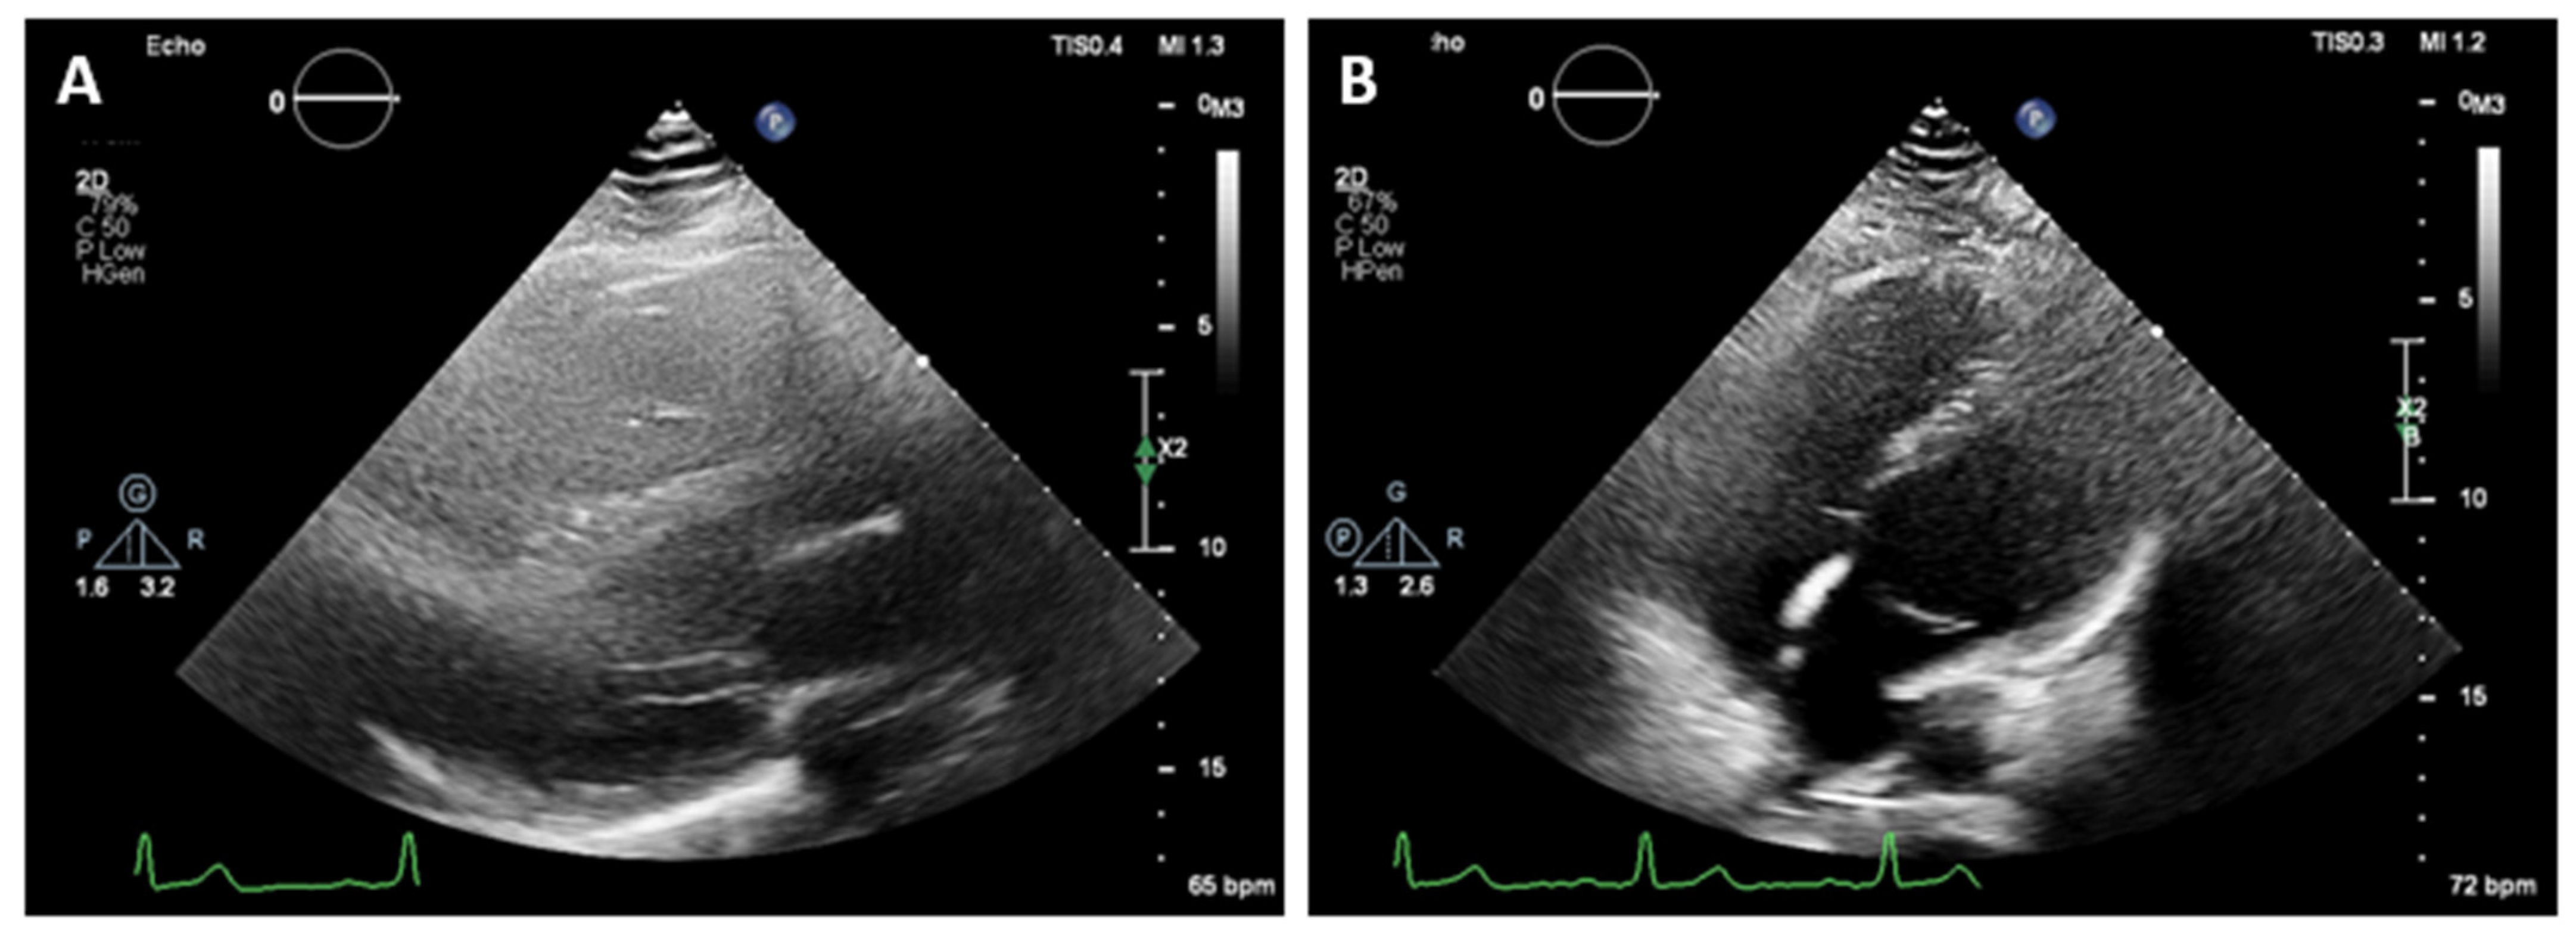

A 36-year-old male with first grade essential arterial hypertension with good medical control was referred for routine cardiovascular exam. He had a medical history of heart murmur since childhood and has been told to have interventricular communication. No prior medical records were submitted. Physical examination did not demonstrate any cardio-pulmonary abnormalities. An electrocardiogram (ECG) revealed sinus rhythm at 62 bpm, normal axis, poor R-wave progression in the precordial leads and repolarization abnormalities and negative T waves in V1–V4 (Figure 1).

Figure 1.

ECG of the patient.

On 2D transthoracic echocardiography (TTE), an unusual heart position was noted with poor image quality from the standard acoustic windows. The parasternal long axis view gave the impression of right ventricular dilatation. An exaggerated motion of the left ventricular posterior wall was noted with hyperechogenic space behind it, which initially has been thought to be pericardium. The left ventricular apex was displaced laterally and posteriorly and was impossible to be visualized from the standard apical views (Figure 2). The apex was better demonstrated when the patient was not in left lateral but in supine position. The findings raised the suspicion of the atrial septal defect, and the patient was referred for CMR for further evaluation.

Figure 2.

Two-dimensional transthoracic echocardiography. (A)—Parasternal long axis view gave the impression of right ventricular dilatation. Hyperechogenic space behind left ventricular posterior wall. Poor image quality. (B)—It was impossible to visualize the apex of the heart from the standard apical views in left lateral position.